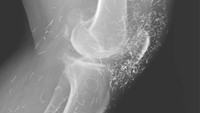

Belum lama ini heboh sebuah temuan dokter terkait ratusan benang 'susuk' emas di lutut seorang pasien wanita 65 tahun di Korea Selatan. Rupanya benang-benang emas itu masuk ke tubuh dari sesi akupuntur yang dijalaninya. (Foto: The New England Journal of Medicine)

Akupuntur dengan benang emas memang populer di Korea Selatan, karena dianggap bisa mengobati osteoarthritis maupun artritis reumatoid. Namun, hingga saat ini belum ada bukti medis berkaitan dengan efektivitas akupuntur dengan masalah kesehatan tersebut. (Foto: The New England Journal of Medicine)